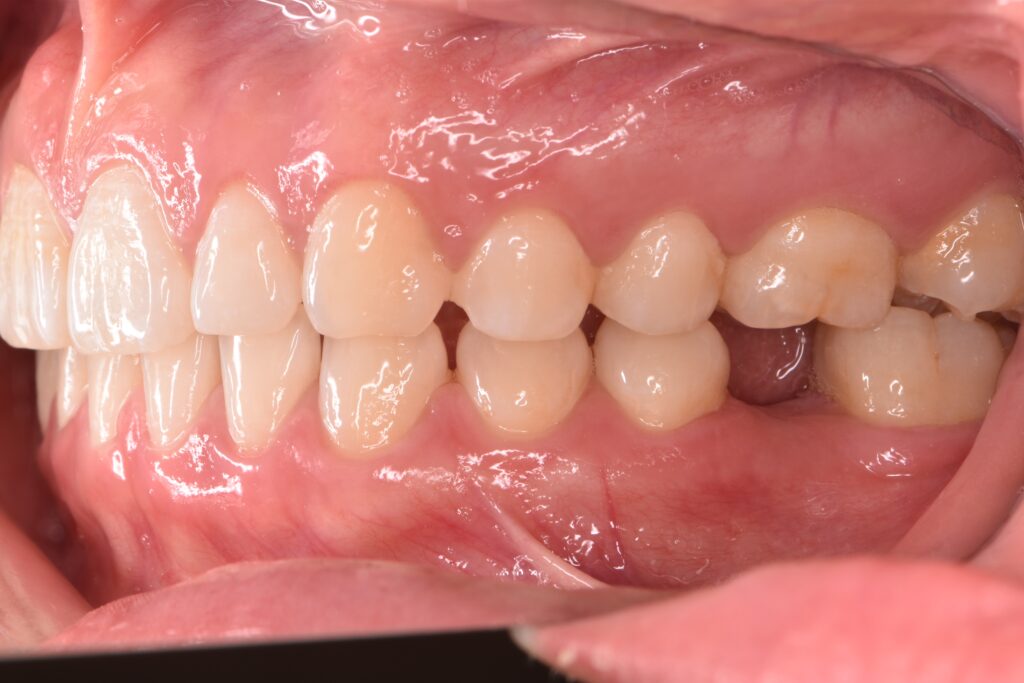

| 備考 | 右上の欠損部へのインプラントを希望で来院されました。 左下のブリッジの下にものが挟まりやすいとのことでブリッジ部分もインプラント埋入を希望されました。口腔内の銀歯も全て綺麗にやりかえたいとのことで、ダイレクトボンディングやセラミックインレーやジルコニアクラウンでやりかえていきました。 右上6番のインプラント埋入時にはソケットリフトで骨造成を行なっています。 見た目だけではなく噛みやすくなりとても満足されています。現在はエアフローのクリーニングやホワイトニングで通院されています。 |